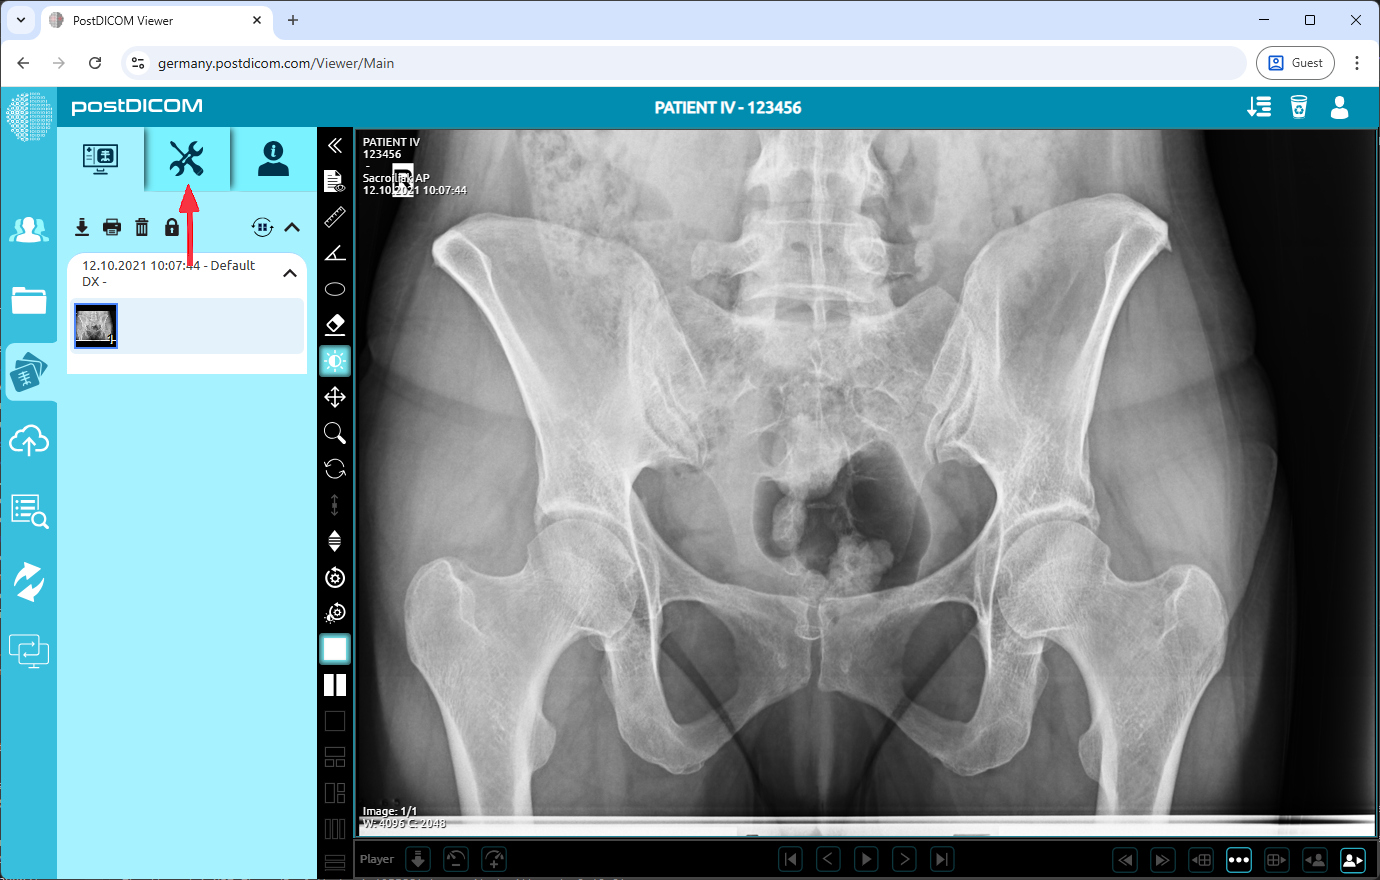

On the “Patient Search” page, all patient orders in your account will be shown. Double-click on the order you want to view the images. The “View” page will be opened. Click on the “Tools” icon on the upper left side of the page.